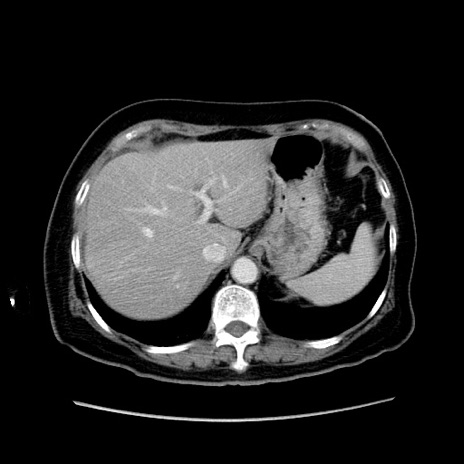

症例19(横断像)

【症例】80歳代女性

【主訴】下腹部痛

【現病歴】約8時間前より下腹部痛の出現あり、救急外来受診。

【既往歴】両側付属器切除

【身体所見】意識清明、下腹部正中に手術痕あり、その部位に一致して圧痛と反跳痛あり。腸蠕動音は亢進。

【データ】WBC 9300、CRP 0.15